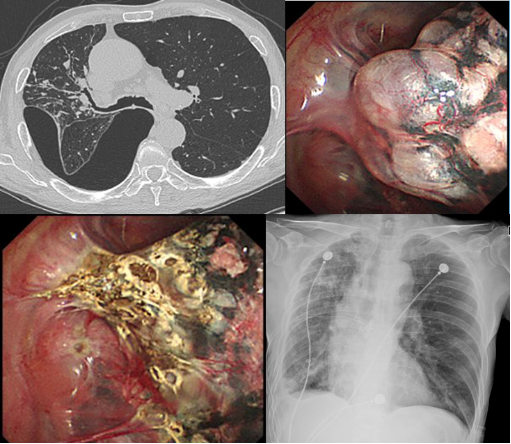

图4.消失肺综合征:患者术前术后胸部CT变化及胸腔镜下巨大肺大疱的表现